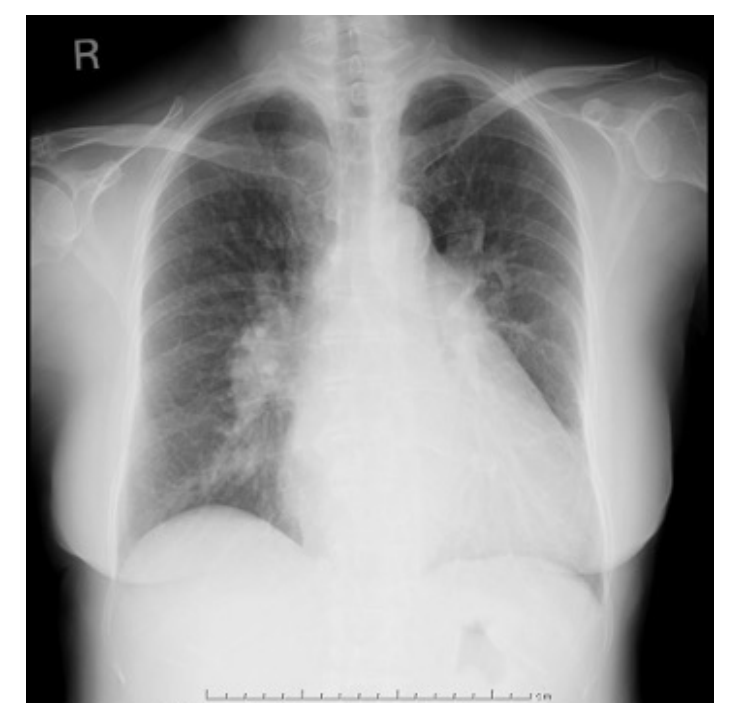

This patient was a 67-year-old woman who had been caught in a cultivator and had her right leg amputated in the 1980s. She had no medical history of congestive heart failure or shortness of breath. She was administered direct oral coagulant, a β-blocker, and a proton pump inhibitor because of chronic atrial fibrillation. Twenty-seven years after the accident, she presented to our hospital because of a swollen left leg and shortness of breath. Her blood pressure was 125/82 mmHg, heart rate was 100/min with atrial fibrillation, and saturation was 95% in room air. The results of a complete blood test as well as renal, liver, and thyroid function tests were all normal but the serum BNP level rose to 607.1 pg/mL. Chest radiography confirmed cardiac dilation, pulmonary congestion, and pleural effusion (Figure 1). She was given 20 mg/day furosemide to treat congestive heart failure. We confirmed a bruit at her left groin and pulsations in a lower leg vein. Transthoracic echo cardiography (TTE) showed an ejection fraction of 55%, her right ventricular pressure increased to 44 mmHg, and severe tricuspid valve regurgitation was detected. Vascular echo showed an arteriovenous fistula (AVF), shunt flow, and an expanded femoral vein (Figure 2). A computed tomography (CT) angiography was performed and revealed a left medial femoral circumflex artery (MFCA)–left common femoral vein (CFV) fistula (Figure 3).